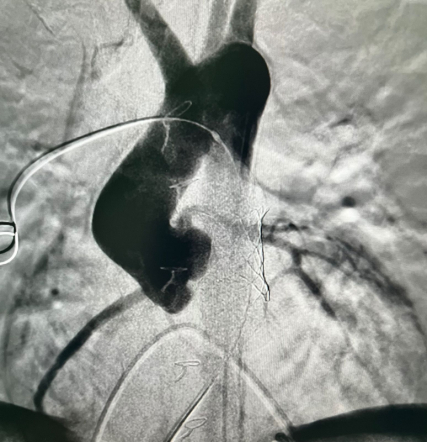

Как пояснил заведующий кардиохирургической службой клиники Педиатрического университета Андрей Нохрин, у Максима из ЛНР был врожденный стеноз аортального клапана. В 2009 году ребёнку провели баллонную дилатацию – расширили просвет клапана аорты с помощью специального катетера. Спустя год процедуру потребовалось повторить. В 2014 мальчику выполнили операцию Росса – заменили аортальный клапан собственным лёгочным клапаном. На место клапана лёгочной артерии имплантировали так называемый кондуит – трубку с клапаном из специальных материалов – дакрона и гортекса.

В 2021-м у пациента развился стеноз клапансодержащего кондуита, но врачи смогли разрешить ситуацию методом баллонной ангиопластики. Однако в последующие годы вновь возник стеноз в этой же зоне, что привело к повышению давления в правых отделах сердца и сердечной недостаточности. Ребёнку требовалось высокотехнологичное лечение, и в ходе консилиума под руководством ректора СПбГПМУ Дмитрия Иванова было принято решение о госпитализации Максима в федеральную клинику вуза.

У пациента из Луганской Народной Республики просвет ранее имплантированного кондуита составлял 1,5 сантиметра, поэтому рентгенхирурги на первом этапе расширили его методом баллонной дилатации. При этом был риск разрыва сосуда, поэтому, чтобы избежать возможных осложнений, медики сначала имплантировали стентграфт – металлический каркас, покрытый герметичным полимером. Просвет кондуита удалось расширить до необходимого диаметра. Затем через бедренную вену хирурги доставили к сердцу искусственный биологический клапан лёгочной артерии Myval индийского производства.